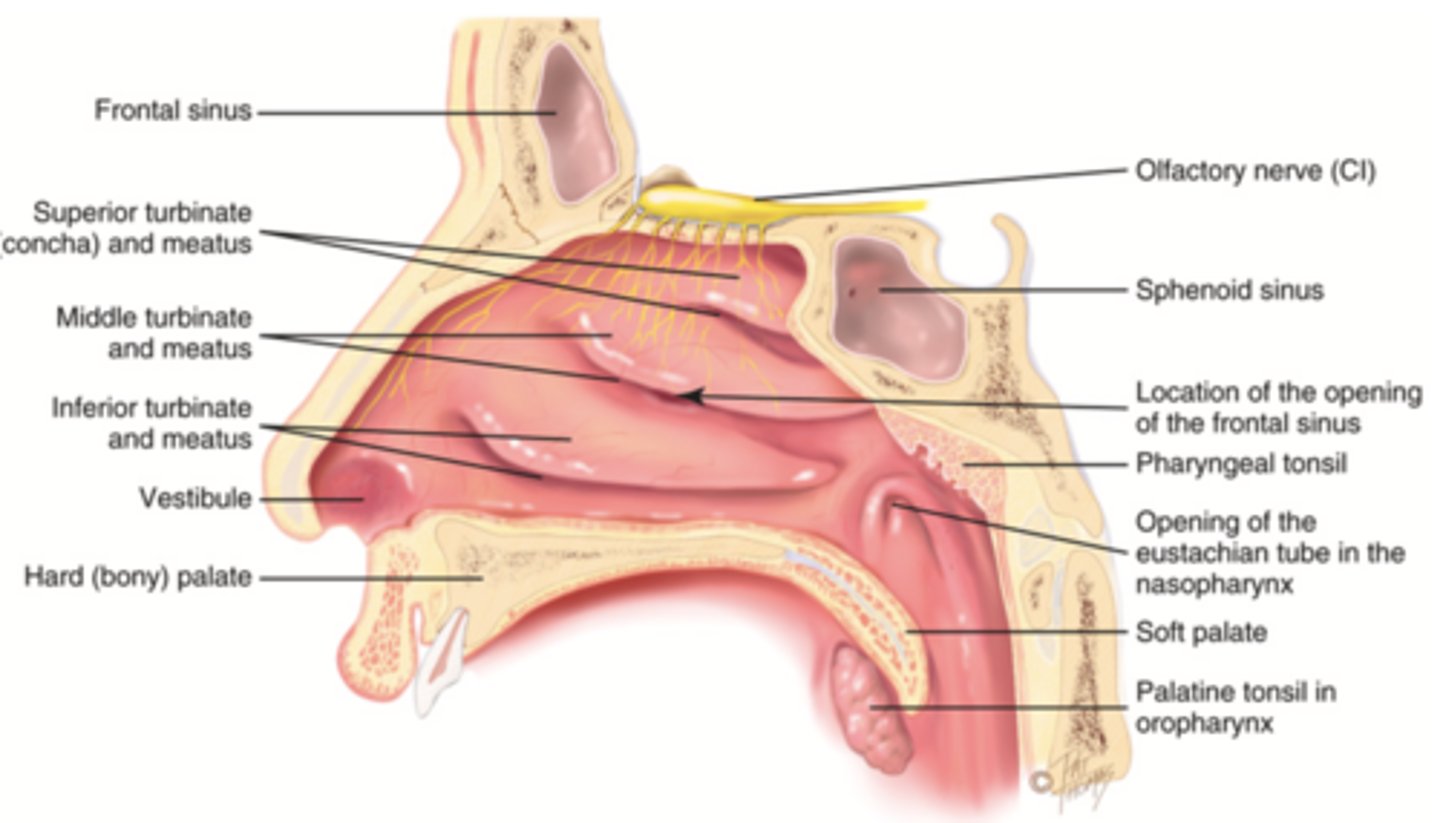

Nasal Cavity

Hollow space behind the nose

Turbinates (Conchae)

- Bones that protrude into the nasal cavity- that increases surface area for filtering dust and dirt particles by the mucous membrane

- There's an inferior, middle, and superior one (2.), 3.), 4.))

Olfactory Region

A dime-sized area at the top of each nasal cavity that houses sensors responsible for smell (1.))

Hard (Bony) Palate

Anterior palate portion that is supported by the palatine processes of the maxillae and the palatine bones (8.))

Meatuses

- Constricted passageways in the nasal cavity that produce air turbulence

- There's an inferior, middle, and superior one

(5.), 6.), 7.))

Soft Palate

Posterior palate portion, not supported by bone (9.))

Paranasal Sinuses

- Frontal

- Ethmoid

- Sphenoid

- Maxillary

Frontal Sinus

Cavity within the frontal bone (yellow)

Ethmoid Sinus

Mucosa lined air spaces located above the sphenoid sinus and below the frontal sinus (purple)

Sphenoid Sinus

Sinus above and behind the nose (green)

Maxillary Sinus

Nasopharyx

The portion of the pharynx that extends from the nostrils to the soft palate

Oropharynx

Central portion of the pharynx between the roof of the mouth and the upper edge of the epiglottis